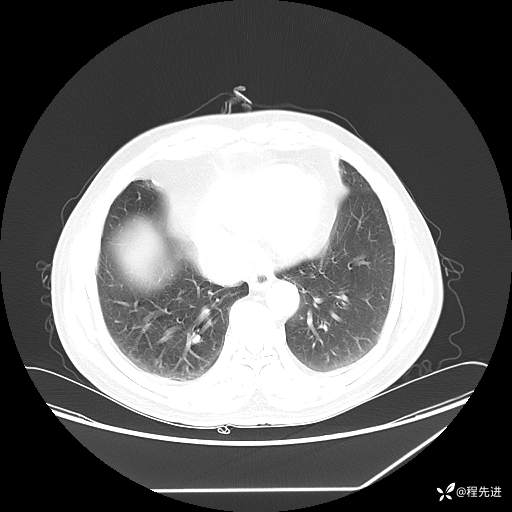

患者性别:男

患者年龄:57岁

简要病史:声嘶2月余

CT平扫+增强: